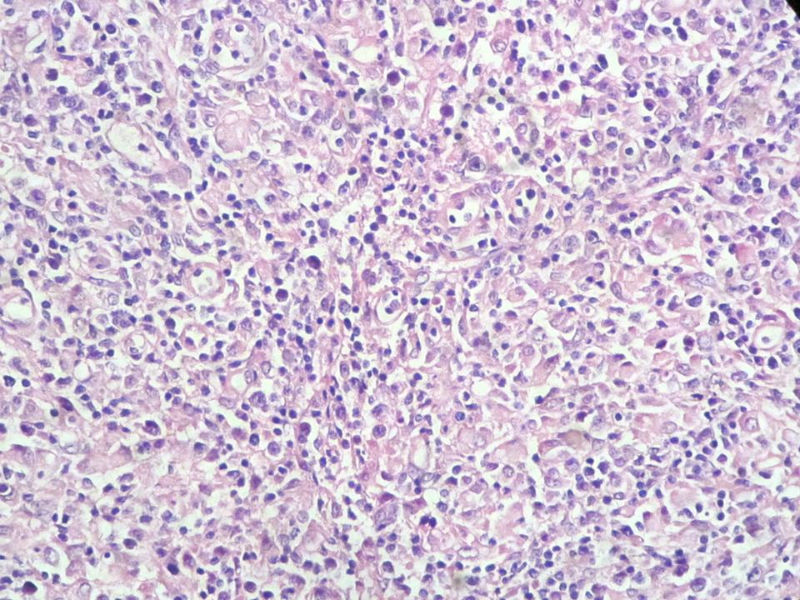

该患者可能存在病毒的感染,抑或是EB病毒的感染,包括CD30+的细胞在内,夹杂在组织细胞、小淋巴细胞之间的一些个大细胞是活化的淋巴细胞,表型看来属B细胞。整个形态呈反应性增生的形态。

请看下图,显示的细胞比较杂,胞浆较丰富,胞核没有什么特别的异型性。没有促纤维增生反应和围血管生长表现,没有肿瘤性坏死,没有见到更多的核分裂,特别是病理性核分裂。因此认为,本例是淋巴组织反应性增生,可能是对病毒感染的反应。